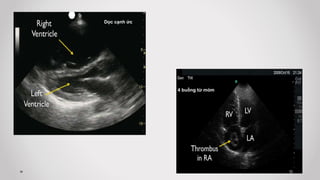

a) Mặt cắt dọc cạnh ức (Parasternal long axis plane)

 Bước 1: Khảo sát “PUMP – Máy bơm”

d) Mặt cắt bốn buồng từ mỏm tim (Apical 4 chambers view)

Ứng dụng lâm sàng….

Dưới mỏm mũi kiếm

1. Tràn dịch màng ngoài tim – Chèn ép tim cấp

4 buồng từ mỏm

RV

LV

Dọc cạnh ức

2. Đánh giá chức năng thất Trái

3. Kích thước – Hình dạng thất Phải

- Bình thường kích thước: Thất (T)/ Thất (P) = 1/0,6

- Hình dạng thất (P) bình thường là hình

bán nguyệt (Crescentic shape) ở mặt cắt

dọc cạnh ức và hình thang (Triangular

shape) ở mặt cắt 4 buồng từ mỏm